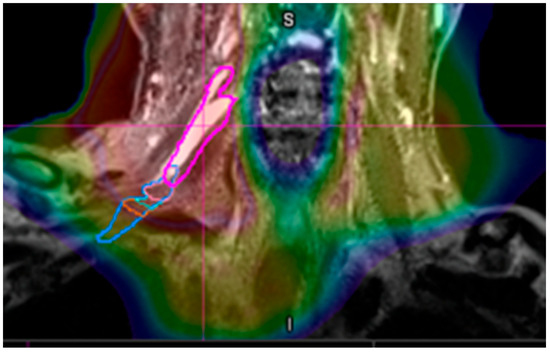

4. Results